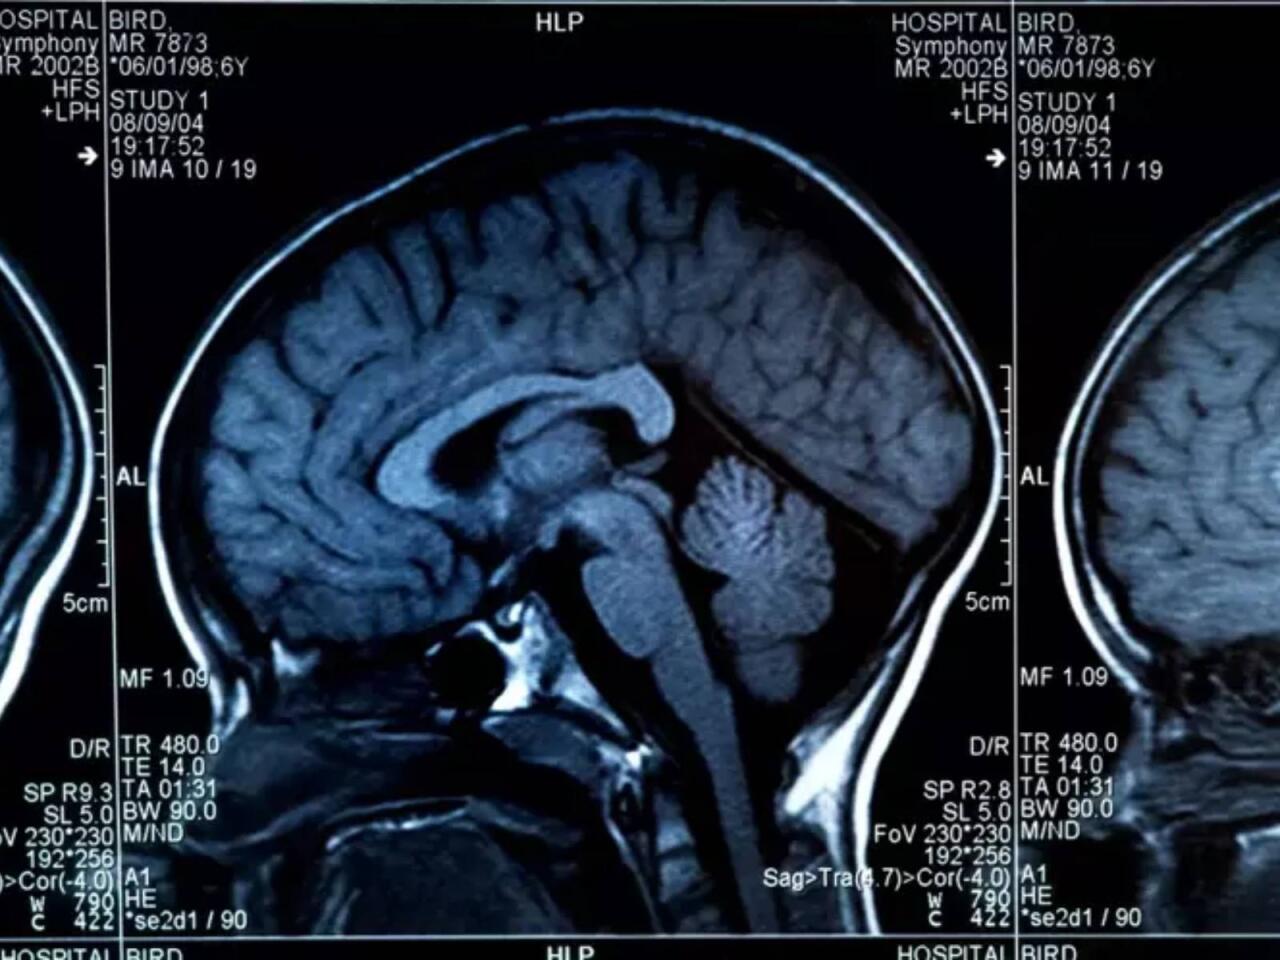

Beynin sağlamlığını təhlükəyə atan 8 qida açıqlanıb.

Son.az xəbər verir ki, aşağıdakı qidaların çoxluğu beynin sürətini zəiflədir.

Uzunmüddətli spirt istifadəsi qərarvermə və impulsları idarə edən beyin bölgələrinə zərər verə bilər. Davamlı alkoqol qəbulu erkən Alzheimer riskini yüksəldir.

Trans və doymuş yağlar

Marqarin, qızardılmış yeməklər LDL xolesterolu yüksəldərək iltihabı artırır və Alzheimer, depressiya riskini böyüdür.

Çox kafein

Gündə 400 mq kafein adətən təhlükəsiz sayılır, lakin 6 fincandan çox qəbulu riski artırır. Ölçülü istehlak vacibdir.

Aşırı natrium

Hazır şorbalar, souslar və konservləşdirilmiş məhsullar çox miqdarda natrium ehtiva edir. Bu, qan təzyiqini yüksəldərək beyinə gedən qan dövranını məhdudlaşdıra və yaddaş problemlərinə səbəb ola bilər.